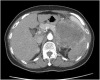

Ovarian granulosa cell tumor (GCT) is a malignant tumor with slow progression. The recurrence of granulosa cell tumor often happens after 5 years, leading to a 'forgotten tumor' by the patient. We present the case of a 64-year-old woman with a presentation of left flank pain. An initial computed tomography scan revealed a single tumor with multiple adjacent organ invasions. Surgical intervention was prescribed and the pathological results revealed a metastatic granulosa cell tumor. We also review the literature for the follow-up and further management of this tumor.